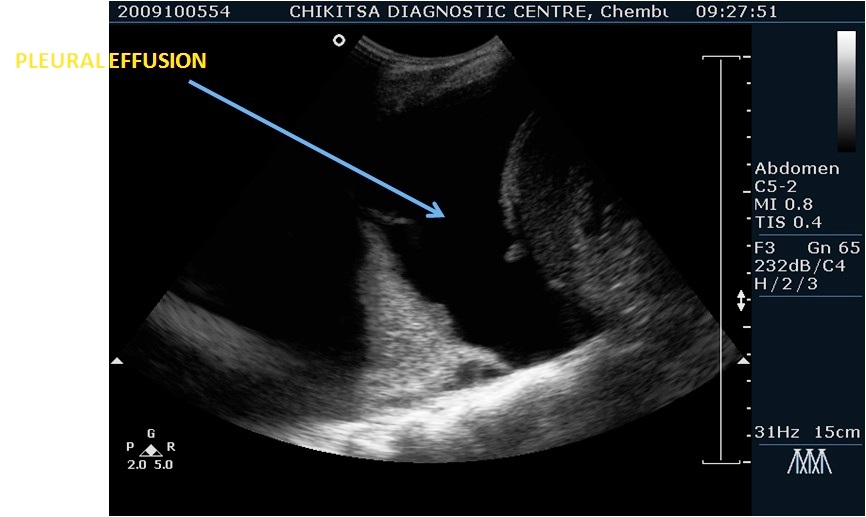

Neonatal sonography is quite different from sonography of the adults. It includes neonatal cranial (brain ) ultrasound, neonatal urogenital ultrasound, neonatal abdomen ultrasound, neonatal chest ultrasound, neonatal hip ultrasound and other specialised ultrasound examinations.